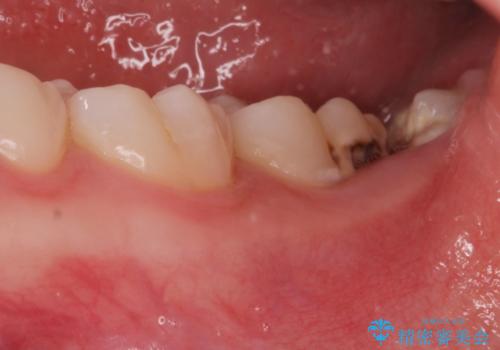

- 左下奥歯が痛いとの事で来院。

親知らずが炎症を起こしていたので抜歯をし、手前の歯は拡大鏡下で虫歯を取り除き、ジルコニアクラウンで治療をしました。